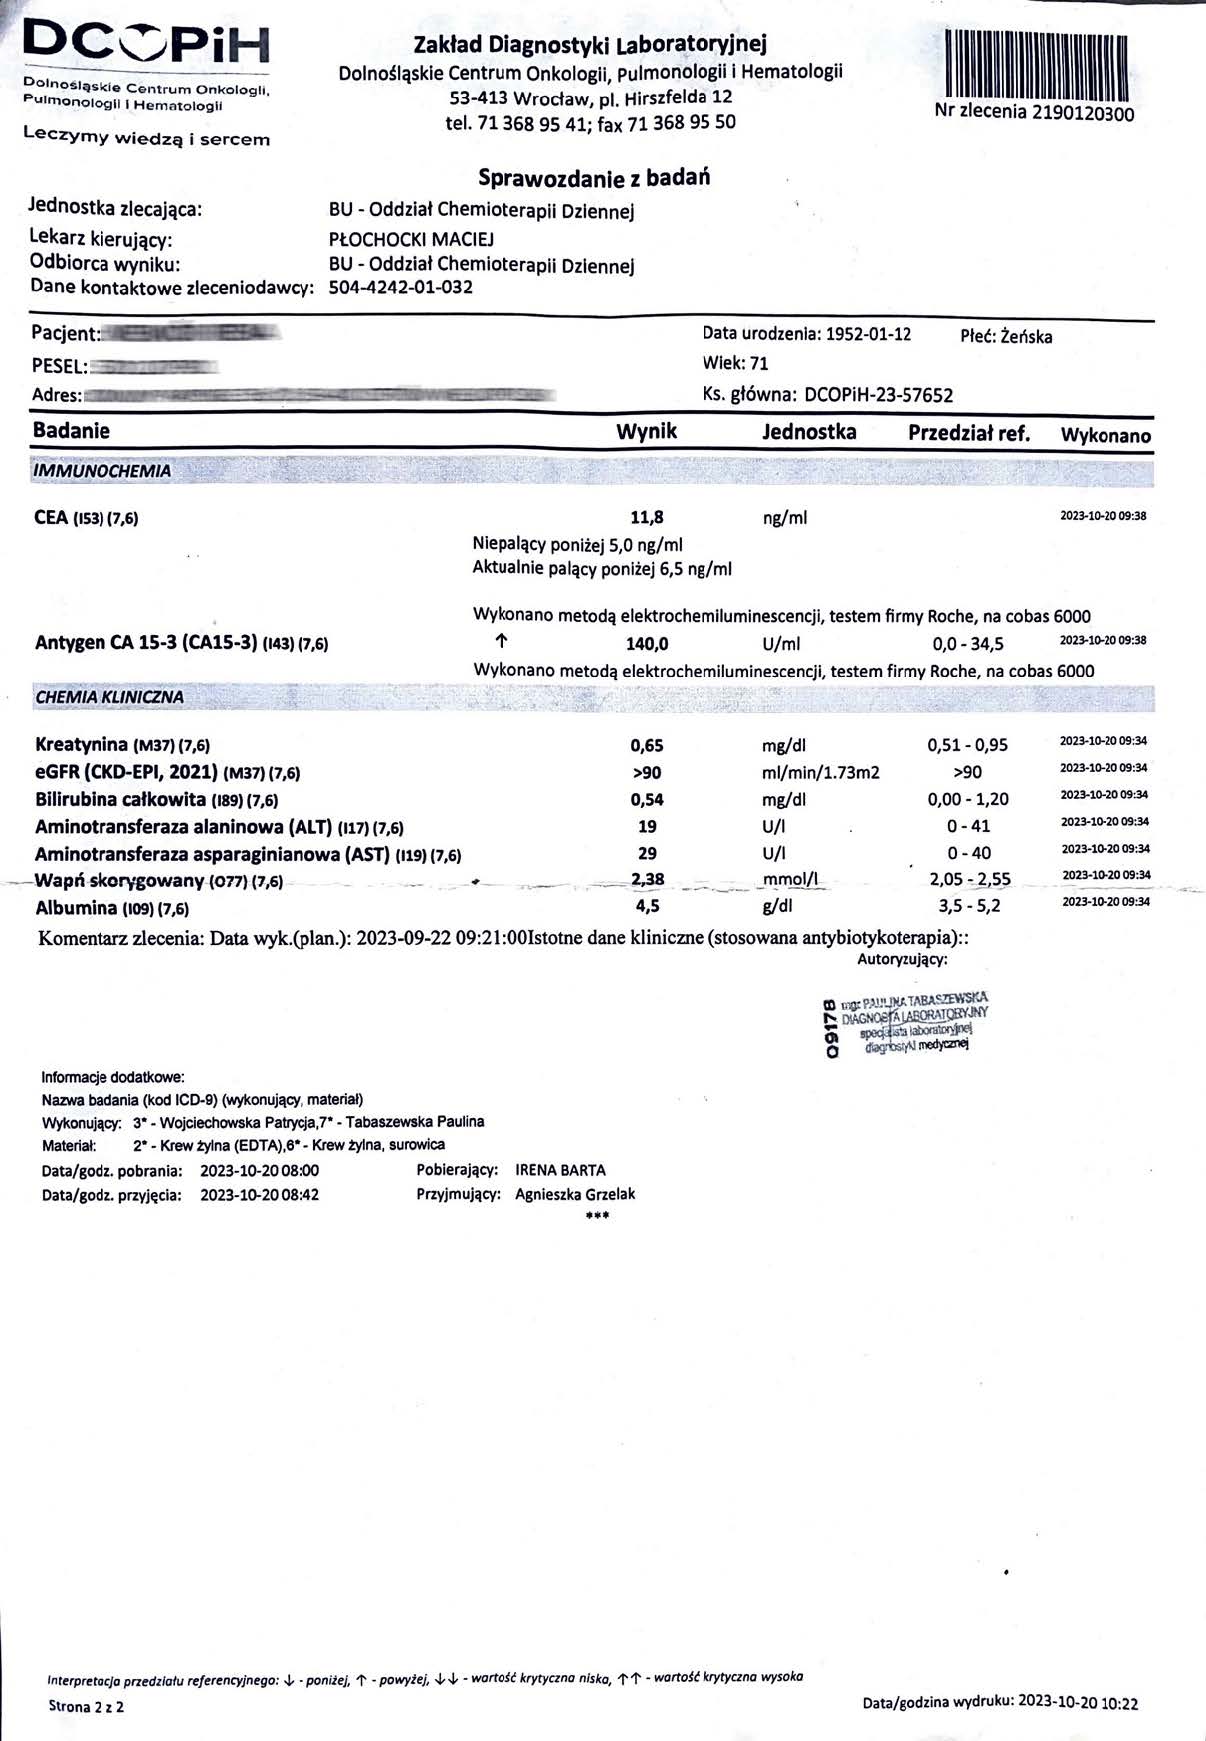

EFEKT PREPARATU NA RAKA PIERSI

Kobieta lat 71, rak piersi w IV stadium, zaawansowane stadium metastazy. W trakcie stosowania preparatu odnotowano spadek markerów Ca 15-3 z wartości 140,0 U/ml do 78,3 U/ml oraz spadek markeru CEA z 11,8 ng/ml do 8,4 ng/ml w zaledwie 3 miesiące, odnotowano stabilność szpiku. Wyniki wykazują zahamowanie progresji, dodatkowo odnotowano cechy uzupełniające terapię farmakologiczną, więc jest to jeden z przykładów wspomagania leczenia systemowego.